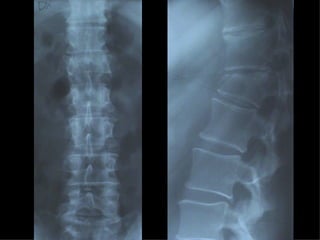

Fratture della colonna vetebrale

Tc pre op

frattura

TC RMN

Rx post